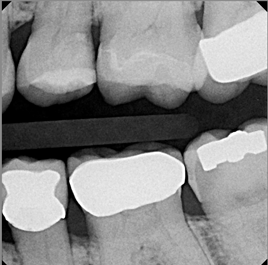

A 66 year-old female patientpresented with a "stained" occlusal groove in tooth No. 13 that did not "stick" with an explorer tip (Figure 1).  Upon radiographic examination (Figure 2), a rather large carious lesion was discovered that encroached upon the dental pulp.  There were no other clinical or subjective signs to alert the clinician or patient to the extent of the damage that had already occurred in the tooth. Figure 3 through Figure 5 show selective caries removal using a round end plastic polymer bur (SmartBurII, SS White).  Before caries removal, isolation of the operative quadrant was achieved using Isovac (Zyris). Because of its Knoop hardness of 90, SmartBurII allows for removal of infected dentin only, while allowing affected dentin to remain for potential remineralization with a bioactive liner or base material.

Once selective caries removal was complete, without a direct exposure of the dental pulp, a sectional matrix, wedge, and ring were placed to begin the restorative process (Garrison 3D Sectional Matrix, Garrison Dental Solutions) (Figure 6).  A bioactive pulp protectant/liner (TheraCal LC, Bisco Dental Products) was placed on moist dentin to a thickness of about .5 mm, then light cured (Figure 7).  The remainder of the preparation was filled using a bulk fill packable composite material, sculpted to proper anatomic form, and light cured (Figure 8).  Figure 9 shows the final radiograph after restoration of tooth No. 13 was completed.  The tooth is planned to be checked clinically and radiographed every 2 to 3 months for the first year postoperatively to make certain that the tooth is responding favorably to the vital pulp therapy.

Fig. 2. A radiographic view of the extensive carious lesion on the distal of tooth No. 13.

Figure 2

Fig 9.	A vertical bitewing radiograph of tooth No. 13 after the restoration is completed.  The tooth will be monitored clinically and radiographically for symptoms over the next 12 months to determine if root canal therapy will ultimately be necessary.

Figure 9